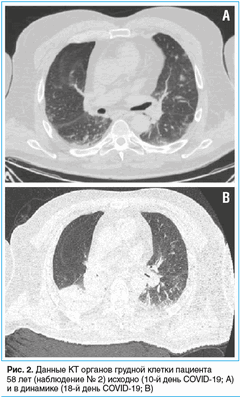

При поступлении: температура тела 36,5 °C, SpO2 при дыхании комнатным воздухом 97%, ЧДД 18 в минуту, ЧСС 100 в минуту, АД 140/80 мм рт. ст. ИМТ 38,1 кг/м 2 . Пациент имел в анамнезе артериальную гипертонию, принимал эналаприл. Неврологический осмотр: нарушение чувствительности по полиневритическому типу, сенситивная атаксия без изменений мышечной силы. На КТ органов грудной клетки определялись субплеврально расположенные участки интерстициальной инфильтрации по типу матового стекла, поражение легочной ткани составляло 15% (рис. 2А). РНК SARS-CoV-2 из материала орофарингеального мазка методом ПЦР-РВ не обнаружена.

Повторная КТ органов грудной клетки: ателектаз нижней доли правого легкого, положительная динамика в виде субтотального регресса двусторонней полисегментарной вирусной пневмонии (рис. 2B). В общем анализе крови — лейкоцитоз (22,8×10 9 /л), преимущественно за счет нейтрофилов (20,4×10 9 /л). Был диагностирован диффузный двусторонний эндобронхит, начата антибактериальная терапия эртапенемом. Неоднократно рецидивировала фебрильная лихорадка (40,0 °C), которую не удавалось снизить антипиретическими препаратами; для достижения управляемой нормотермии применялся аппарат Arctic Sun.